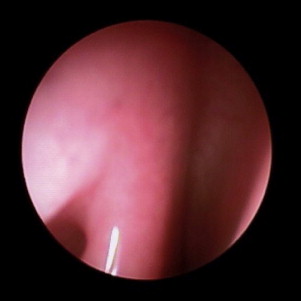

The organs of olfaction are unique within the human body because they contain neuroepithelium that regenerates. However, these delicate nerve fibers may also be damaged and undergo permanent loss. Grossly, the nasal passages contain the structures of olfaction, which include the upper nasal septum, and middle and superior turbinates. These structures facilitate airflow and contain the primary olfactory neurons. Olfactory molecules dissolve in mucous overlying these neurons and then interact with the neurons, producing an action potential. The olfactory bulb, which is positioned at the anterior cranial fossa, serves as the initial transfer station in the olfactory pathway ( Fig. 1 ). The primary olfactory neurons synapse with secondary neurons, which constitutes aggregates referred to as glomeruli. The olfactory cleft lies in a protected location approximately 7 cm from the nasal sill ( Fig. 2 ). Olfactory bulb comes from the Latin words olfactus , which means sense of smell, and bulbus , which means swollen root. This region is where the olfactory nerves (cranial nerve I) terminate and the olfactory tracts arise.